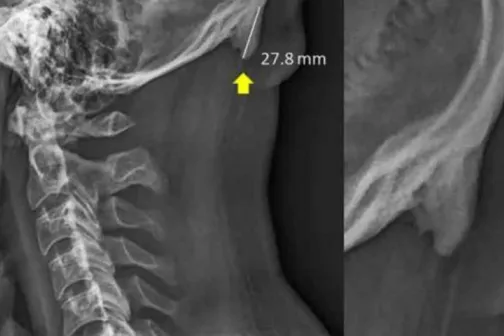

Imagine 21/06/2019 -15:33 Sănătate Studiu alarmant: tinerii dezvoltă niște ,,coarne” la nivelul craniului, din cauza utilizării prelungite a telefonului mobil